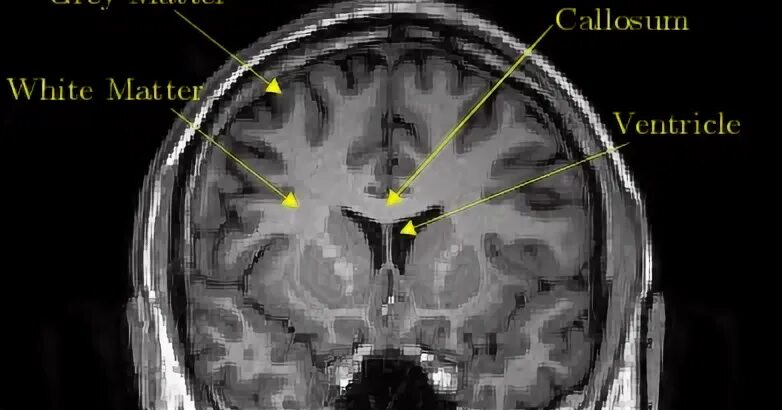

Grey matter